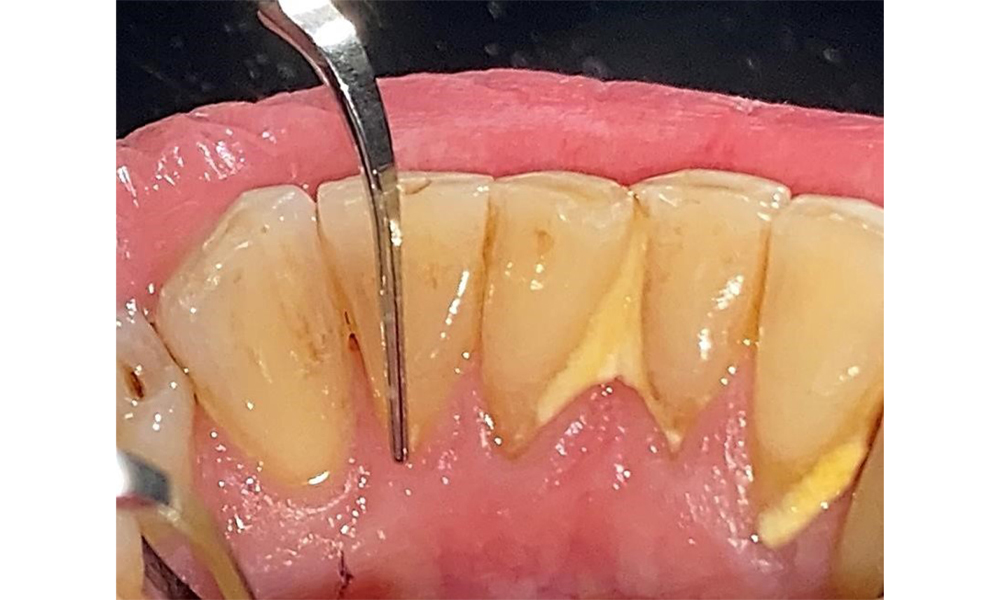

Сондиране за документиране на резултатите медиопалатинално на зъб 27.

Фиг. 8: Сондиране за документиране на резултатите медиопалатинално на зъб 27. © д-р Р. Крапф